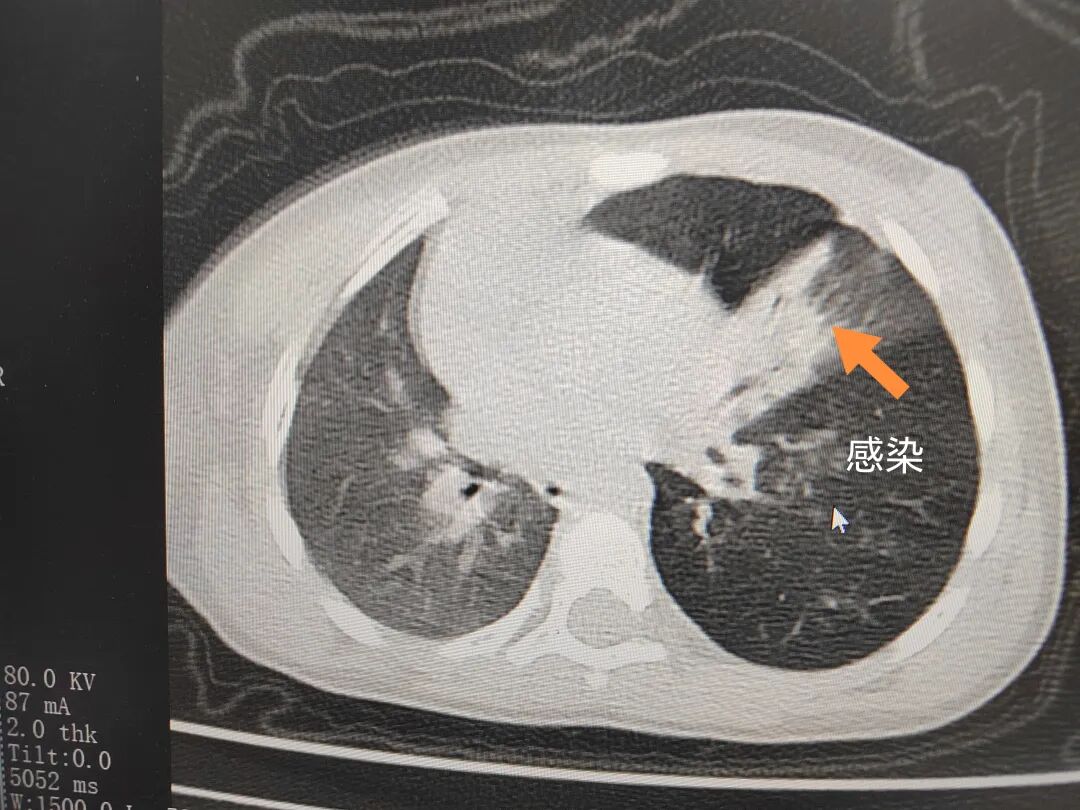

三天后(11月13日),趙寶出現(xiàn)高熱、咳喘加重,家長著急了,再次帶他來到醫(yī)院。CT檢查顯示左肺過度充氣,左肺上下葉支氣管主干見不規(guī)則高密度影,左肺上葉可見大片狀密度增高影,縱隔窗實(shí)變,提示為“左側(cè)支氣管內(nèi)異物并繼發(fā)性改變,左肺上葉舌段肺膨脹不全”。

市二院小兒呼吸內(nèi)科副主任楊亞娟介紹,異物誤入氣道可能導(dǎo)致氣道阻塞,嚴(yán)重時(shí)可引發(fā)窒息,甚至危及生命。若異物進(jìn)入支氣管,造成不完全堵塞,可引起阻塞性肺氣腫;如完全堵塞支氣管,則可能導(dǎo)致肺組織萎縮,形成肺不張。此外,若異物存留時(shí)間較長,或?yàn)橹参镄援愇?,容易合并?xì)菌感染,產(chǎn)生膿性分泌物,進(jìn)而發(fā)展為肺炎。她強(qiáng)調(diào),盡早診斷并取出異物,是減少并發(fā)癥、降低病死率的關(guān)鍵。